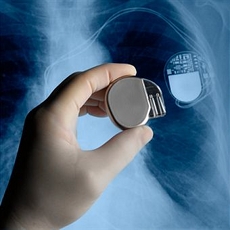

3. PACEMAKER

Em 1956, Wilson Greatbatch estava trabalhando na construção de um dispositivo que gravasse os movimentos cardíacos dos seus pacientes, na Universidade de Bufallo, nos Estados Unidos. No entanto, ele acabou por retirar um fio de uma forma errada. Quando ligou o aparelho, reparou que o mesmo fazia o batimento muito semelhante ao de um coração. Entretanto, Wilson Greatbatch tinha conversado com alguns colegas seus sobre as possibilidades de um aparelho poder estimular os batimentos de um coração. Com isso, inventou um aparelho de apenas 2 centímetros que salva milhões de vidas todos os anos.

Em 1956, Wilson Greatbatch estava trabalhando na construção de um dispositivo que gravasse os movimentos cardíacos dos seus pacientes, na Universidade de Bufallo, nos Estados Unidos. No entanto, ele acabou por retirar um fio de uma forma errada. Quando ligou o aparelho, reparou que o mesmo fazia o batimento muito semelhante ao de um coração. Entretanto, Wilson Greatbatch tinha conversado com alguns colegas seus sobre as possibilidades de um aparelho poder estimular os batimentos de um coração. Com isso, inventou um aparelho de apenas 2 centímetros que salva milhões de vidas todos os anos.